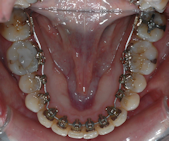

les appareils utilisés en technique linguale (totalement invisibles). Les techniques linguales offrent la possibilité d’un appareil orthodontique efficace et totalement invisible.